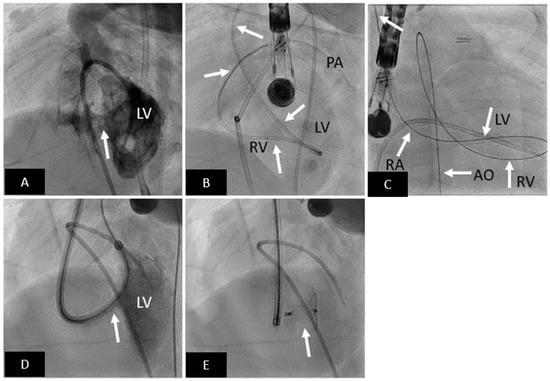

- Opolski, M.P.; Michałowska, I.M.; Borucki, B.A.; Nicińska, B.; Szumowski, Ł.; Sterliński, M. Augmented-reality computed tomography-guided transcatheter pacemaker implantation in dextrocardia and congenitally corrected transposition of great arteries. Cardiol. J. 2018, 25, 412–413. [Google Scholar] [CrossRef]